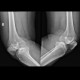

Selamat pagi sejawat, mohon bantuan arahan untuk kasus pasien wanita 64 tahun dengan keluhan lutut kanan bengkak dan nyeri jika berdiri lama, atau digunakan berjalan jauh.

Membaik saat istirahat dan menggunakan Cox-2 inihibitor.

dengan pembacaan radiologi: OA Lutut Kanan grade 3.